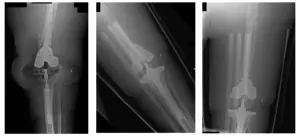

X-Rays show preoperative changes of left TKA reconstruction

Pre-operative Scanogram show mild degenerative changes at both hips and right knee

There is an orthopedic plate and multiple screws in the right distal femur.

Pre-Surgical X-Rays show left TKA dislocation with dorsal translation of the tibia and widening of the tibiofemoral joint